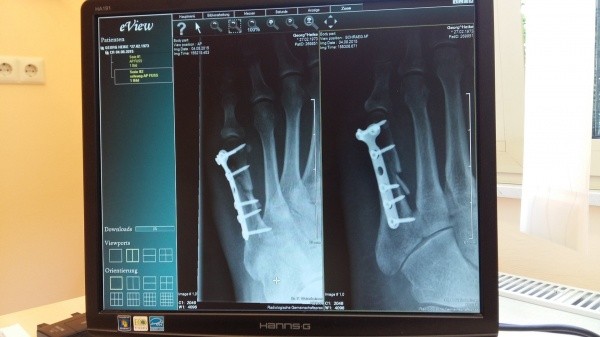

Стоимость современного рентгенодиагностического комплекса «Диаком» превысила 15 миллионов рублей, но он действительно оправдывает вложенные в него деньги. Цифровой телеуправляемый аппарат помогает при всех видах рентгенографических и рентгеноскопических исследований, дает возможность не просто получать цифровые диагностические изображения, но и производить их обработку для дальнейшего сохранения и передачи полученной информации.